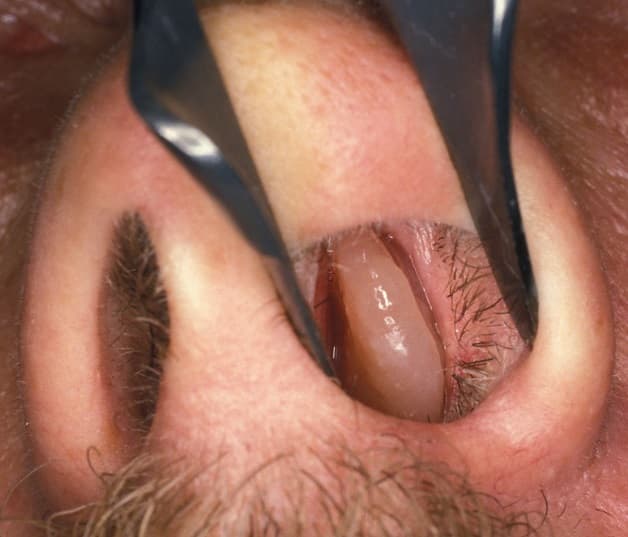

Hình ảnh một polyp xoang mũi

Polyp được hình thành do các mạch máu, niêm mạc ở vùng xoang mũi bị tăng tính thấm nước bị kéo xuống dưới, dần dần hình thành nên những khối mềm gọi là polyp. Polyp thường được hình thành sau các đợt viêm mũi, viêm xoang, hen suyễn kéo dài mà không được điều trị. Bản chất các polyp này hoàn toàn lành tính, không phải khối u có khả năng gây ung thư. Tuy nhiên kích thước của các polyp này sẽ là trở ngại lớn cho chức năng thở của mũi. Đặc biệt với những polyp có kích thước lớn thì phương pháp phẫu thuật để loại bỏ những polyp này được cho là hiệu quả nhất. Phương pháp này cũng giải quyết nhanh chóng những triệu chứng bít tắc đường thở, thở khó, vướng cộm mũi do polyp gây ra.